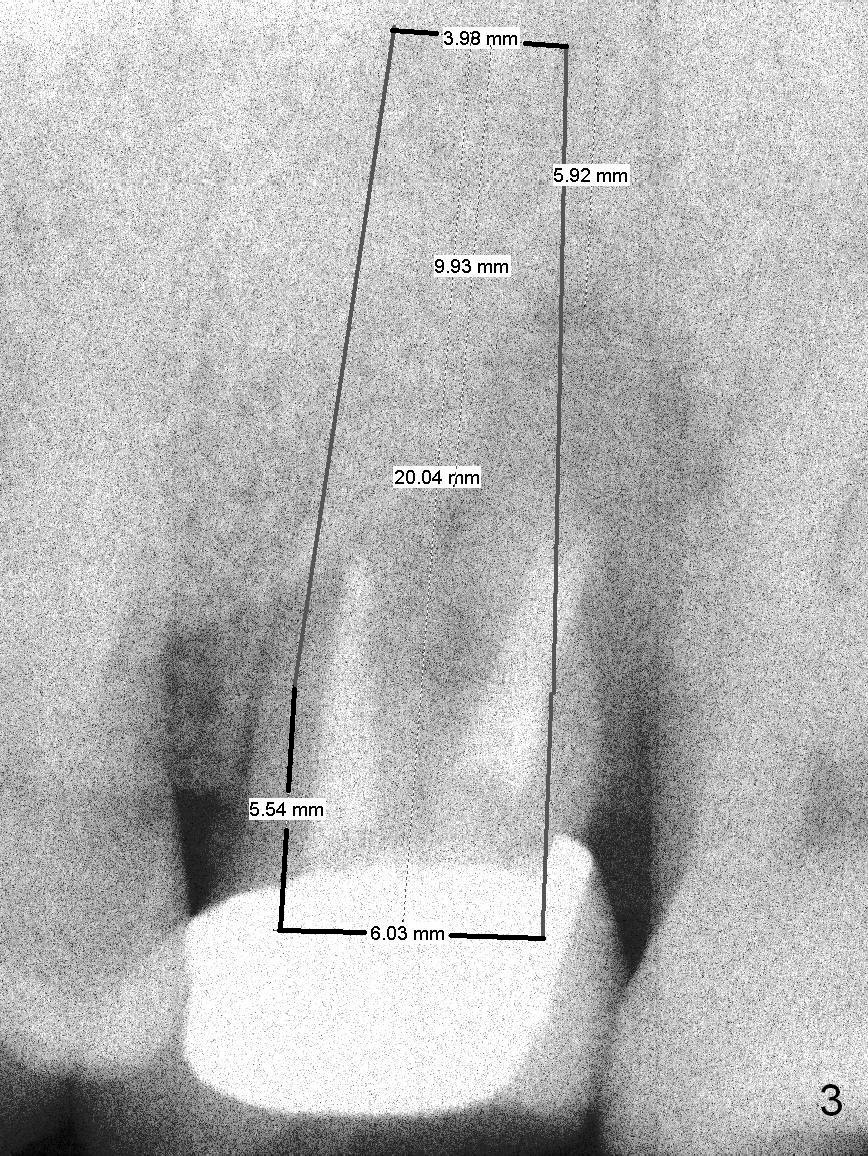

A 47-year-old man (LW) agrees to have the tooth #15 (Fig.1) extracted for implant after 4-year delay (Fig.2). A 20 mm long implant will have at least 6 mm native bone for stabilization (Fig.3). Bone density seems to be high. Use Bicon drill and reamers until 3.5 mm, followed by 5x20 mm Tatum tapered tap and PA.